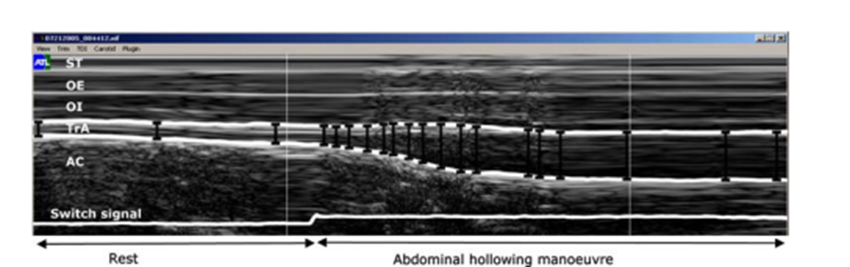

Mannion et al. (2008, 2010)에 2008년도의 연구 논문에 따르면 복횡근의 우선적인

활성화비율( TrA preferential activation ratio)의 차이로 요통의 원인과 기전을 설명하기에

임상적 으로 사용하기에는 지나치게 모호하다고 지적하고있습니다.

요통환자와 대조군환자의 복횡근의 두께 측정표 및 지수 중에서 복횡근의 Abdominal

Hollowing동안의 우선적인 활성화 비율(TrA preferential activation ratio)과 복횡근

근육의 두께차이에 따른 요통유무의 낮은 신뢰성 때문에 임상에서의 사용에 의문이

제기된다고 언급하고있습니다.

외측 복벽두께의 측정값을 신뢰할 수 있습니까?

휴식 시 측면복벽두께의 차이는 증상이 없는 일반인에게도 빈번하게 나타납니다.

그러므로 요통환 자들에게서 나타나는 복부근육두께의 차이는 임상적으로 관련이

없다고합니다.

앞서 언급한 2008년도 요통 환자 그룹(Mannion et al.,2008) 와 무증상 집단 그룹

연구에서의 복벽두께의 차이 범위는 11%-26%으로 높은 표준편차를 보였습니다.

그러므로 임상에서 요통 환자들의 측면 복근 두께의 비대칭을 확대 해석하는 것을

주의해야 한다고 권고하고있습니다.

Mannion et al은 체질량지수(BMI)가 절대적인 복부근육 두께의 예측변수라는 것을

발견했고,휴식 시나 Abdominal Hollowing 시 모든 근육에 있어 30-44%의 변동을

보였습니다.

즉 요통의 유무와는 상관없이 BMI는 지방량에 따른 근육두께의 차이로 복횡근의

우선적인 수축비율에 20 -30%의 변동을 만들수 있습니다.

그러므로 환자에서 보이는 복횡근또는 복부근육의 두께의 비대칭을 판단함에 있어

정상인에게서도 일반적으로 볼수 있는 현상이기 때문에 주의를 기울여야 합니다.